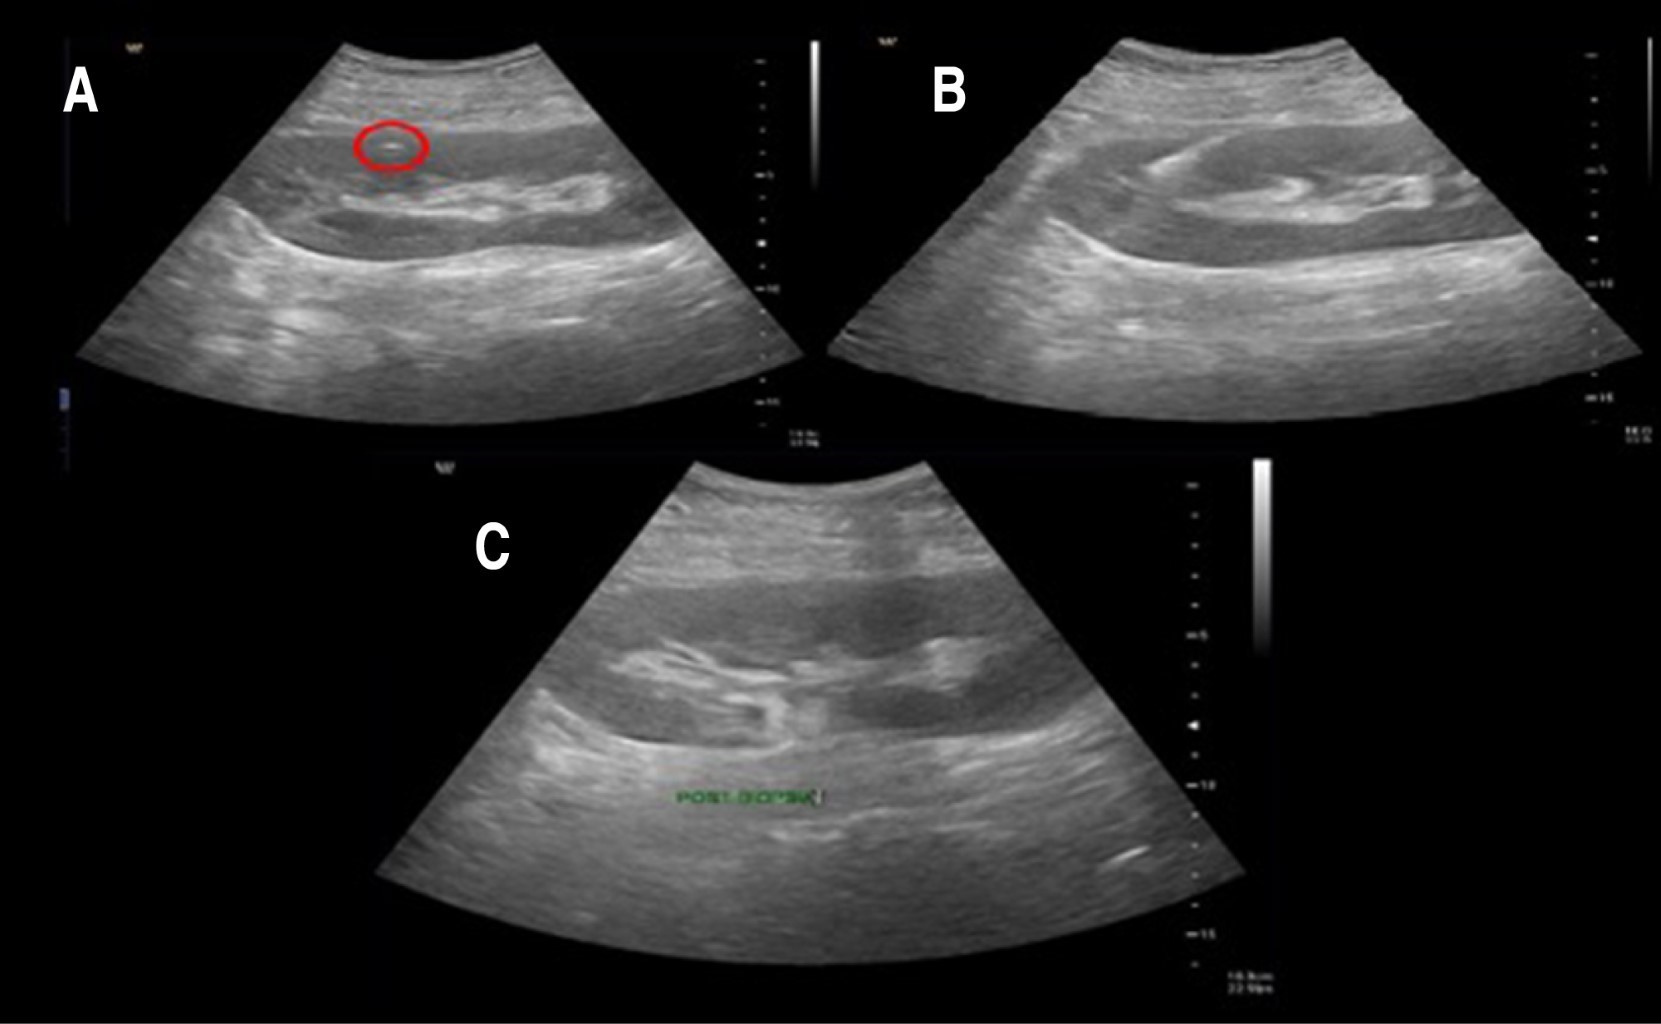

Kidney transplant biops with tangential technique using an ultrasound guided cutting needle

Introduction: renal graft biopsy is the most important tool for the diagnosis of renal pathology. Objective: to describe the experience kidney transplant biopsy with tangential technique using an ultrasound-guided cutting needle. Material and methods: a retrospective review of 89 patients with kidney transplant that required eco-guided biopsy type Trucut with cortical tangential approach technique using automated devices with 18G needles for evaluation of such technique, as well as it success rates for obtaining tissue samples and possible complications that may occur. Results: the cortical tangential technique identified a total of 89 samples, 72 samples (80.9%) were considered satisfactory, as for minimum samples 7 cases (7.9%) and 10 inadequate (11.2%) were found. With the cortical tangential approach, excellent results were obtained, finding satisfactory samples in 32 patients with only one specimen, 33 patients with two specimens and only 7 patients required obtaining a third specimen. There was no distinction between age and sex in the patients evaluated. Only 10 patients (11.2%) had complications, the most commonly encountered being hematuria. Conclusion: the cortical tangential approach is an useful and adequate technique for obtaining a satisfactory histopathological sample, without significant complications.

Figure 2